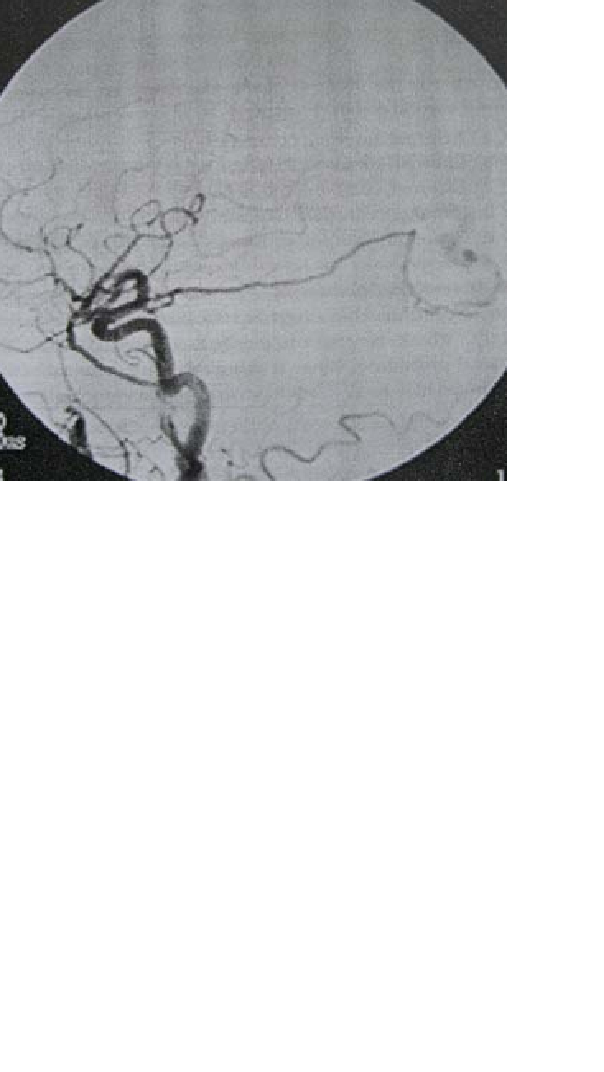

Skenario: Laki-laki berusia 45 tahun dibawa ke ruang gawat darurat dalam keadaan demam, mual, muntah, dan sakit kepala hebat. Lumbar puncture mengungkapkan sel-sel darah merah sedikit

mengalami kenaikan, tapi jumlah protein, glukosa dan sel darah putih semuanya normal, termasuk tidak santokromia. Angiogram pasien tampak di bawah ini..

37. Manakah diantara etiologi di bawah ini yang merupakan etiologi yang paling mungkin merupakan etiologi dari kelainan yang ditunjukkan pada angiogram tersebut.?

A. Trauma kepala

B. Infeksi

C. Pradisposisi genetika

D. Penyakit vaskular kolagen